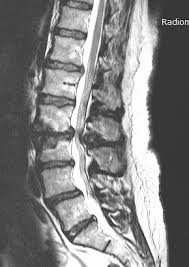

Mrt Bilder Und Befunde